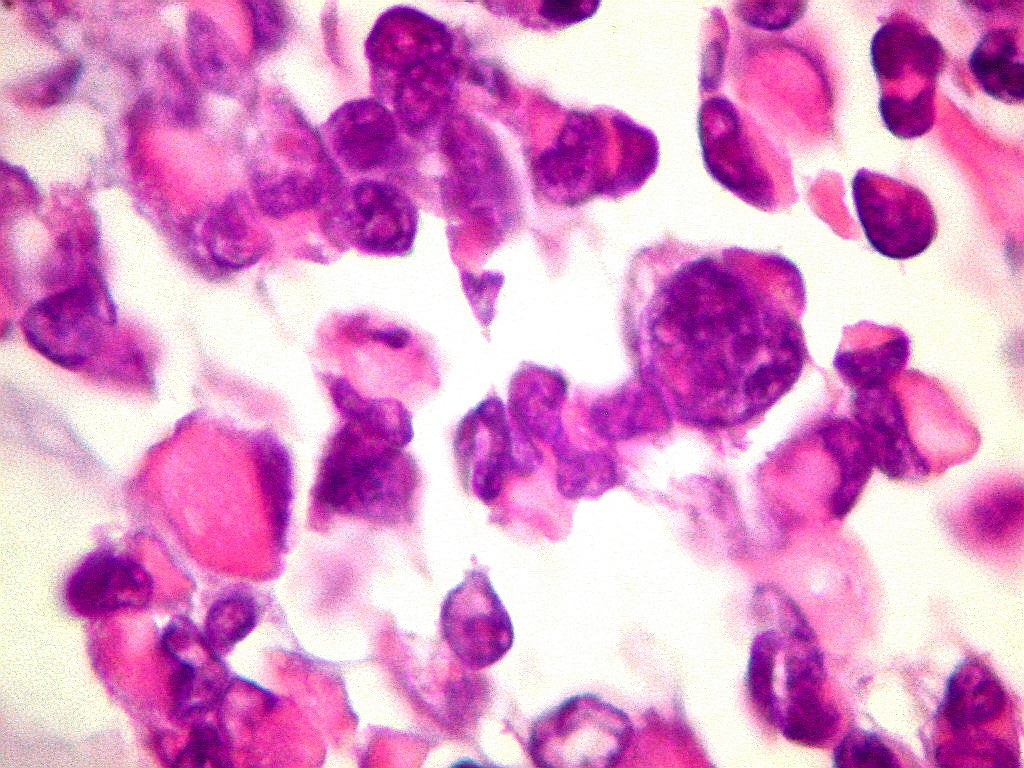

| VIM.

Positiva no citoplasma das células neoplásicas. Filamento

intermediário do citoplasma de expressão ubiquitária. |

Destaca

núcleo excêntrico, deslocado pelo corpúsculo rabdóide. |